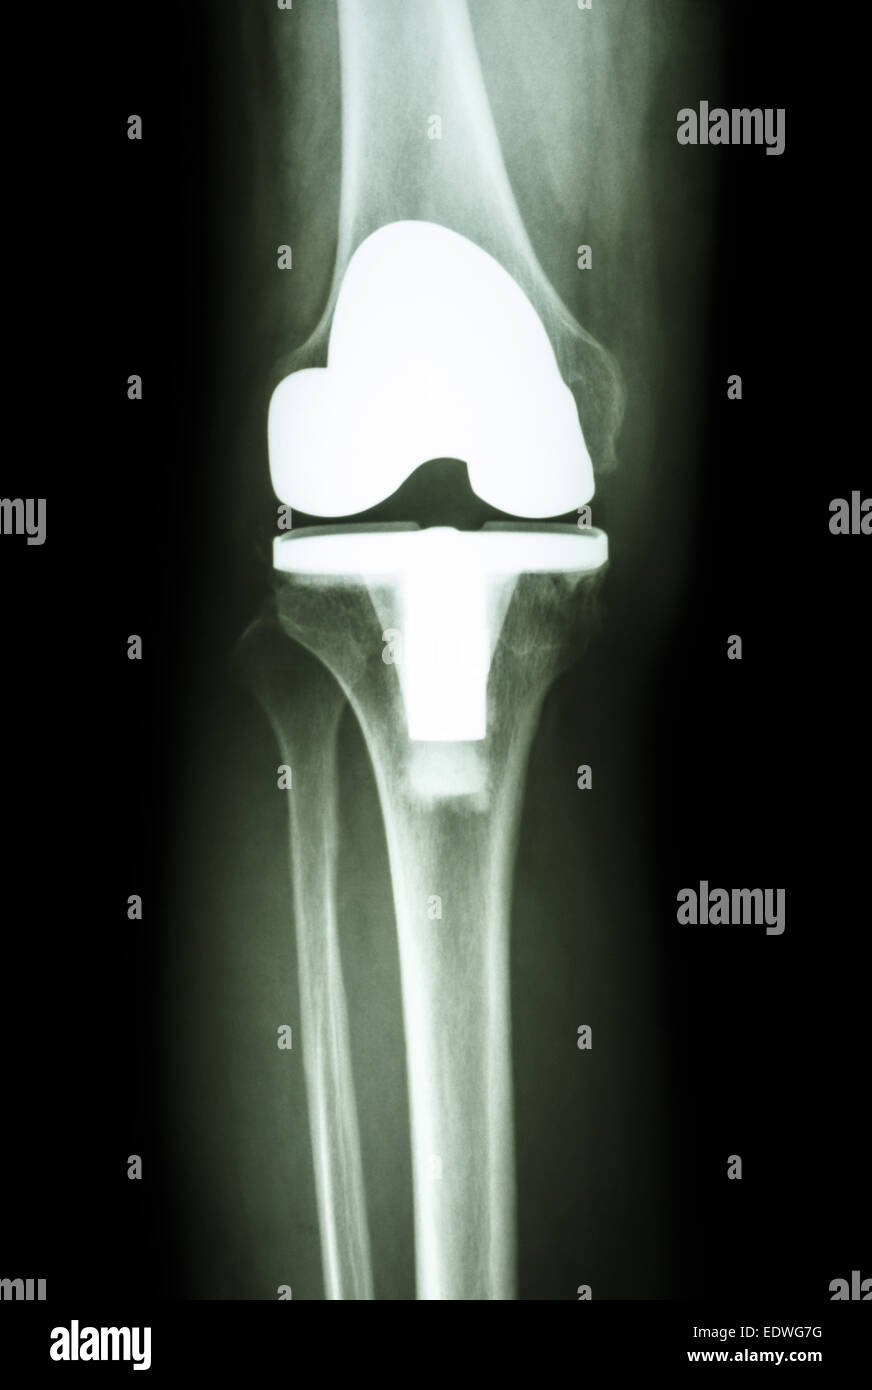

Articulation du Genou prothèse (prothèse articulaire) de l'arthrose patient Banque D'Imageshttps://www.alamyimages.fr/image-license-details/?v=1https://www.alamyimages.fr/photo-image-articulation-du-genou-prothese-prothese-articulaire-de-l-arthrose-patient-77393556.html

Articulation du Genou prothèse (prothèse articulaire) de l'arthrose patient Banque D'Imageshttps://www.alamyimages.fr/image-license-details/?v=1https://www.alamyimages.fr/photo-image-articulation-du-genou-prothese-prothese-articulaire-de-l-arthrose-patient-77393556.htmlRFEDWG7G–Articulation du Genou prothèse (prothèse articulaire) de l'arthrose patient